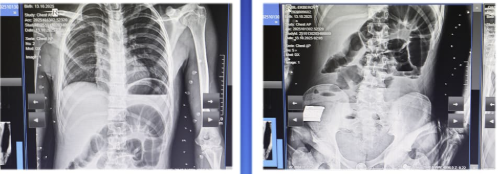

Bildirilib ki, oktyabrın 14-ü 2008-ci il təvəllüdlü yeniyetmə qarın nahiyəsində kəskin ağrı, ürəkbulanma, təkrarlanan qusma və hipertermiya şikayətləri ilə Kliniki Tibbi Mərkəzin Təcili və təxirəsalınmaz tibbi yardım şöbəsinə gətirilib: “Müayinələr nəticəsində xəstəyə peritonit diaqnozu qoyulub və əməliyyatönü hazırlıqdan sonra təxirəsalınmaz cərrahi müdaxilə aparılıb. Həkimlər tərəfindən nazik bağırsaq seqmentinin rezeksiyası, yoğun bağırsağın defektinin tikilməsi əməliyyatı icra olunub.

Əməliyyat zamanı nazik bağırsaqda, iliosekal küncdən 70-80 sm məsafədə, iki yerdə deşici (perforativ) zədələnmə müəyyən olunub. Bu perforasiyalara səbəb bağırsaq mənfəzində yerləşən iti və sərt yad cisim taxta parçası olub. Bundan əlavə, yoğun bağırsaqda da perforativ dəlik və bütün nazik bağırsaq boyunca mənfəz daxilində müxtəlif ölçülü, iti uclu, sərt yad cisimlər aşkarlanıb”.

Qeyd olunub ki, uğurlu cərrahi müdaxilə və 8 günlük stasionar müalicə nəticəsində xəstənin vəziyyəti kafi qiymətləndirilib və o, ambulator müalicə üçün evə buraxılıb.